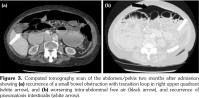

Two months following admission, a routine CT scan revealed recurrence of intra-abdominal free air (Figure 3). However, given her stable symptomatology, it was decided that she did not require re-admission. Treatment of SIBO, which was deemed to have been the cause of her benign PI, was continued with oral antibiotics and since then she has had complete resolution of her abdominal pain and diarrhea.